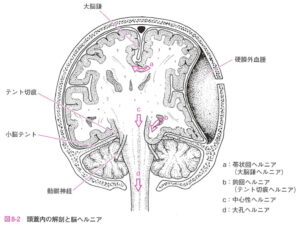

| 病態 | 脳腫瘍などの頭蓋内占拠性病変、脳浮腫、水頭症などによって頭蓋内圧が亢進する状態。 その結果、脳ヘルニアを引き起こす。下行性脳ヘルニアのリスク↑のため腰椎穿刺は禁忌 ![]() 脳ヘルニアとは、大脳鎌の縁、テント切痕、大孔を介して脳組織がシフトすること。 |

| 検査 | 頭部CTで以下の脳ヘルニアの有無を確認(脳幹圧迫があれば危険) 【切迫脳ヘルニアの有無の確認】 切迫脳ヘルニアとは緊急減圧が必要な状態で、具体的にはテント切痕ヘルニアや大後頭孔ヘルニアがある状態のこと。CTにて、大きな占拠性病変、5mm以上の正中偏位、脳底槽の圧迫もしくは消失を認める場合は切迫脳ヘルニアを疑い、以下を確認する。 ![]() |

脳ヘルニアの分類

※3つはまとめてテント切痕ヘルニアという

| 症状 | 予後 | |

| 大脳鎌下へルニア 帯状回ヘルニア |

初期は無症状→前大脳動脈圧迫により対側 or 下肢の運動・感覚障害、前大脳動脈閉塞により脳梗塞を生じる場合がある。必ず鉤ヘルニアに先んじて生じるため、臨床的に重要!![]() CT:Monro孔の圧迫による健側の側脳室の拡大(特に側脳室下角が早期に開大) |

良 |

| 鉤ヘルニア※ | 初期は病変側の動眼神経麻痺(対光反射消失し散瞳→瞳孔不同) さらに進行すると・・・↓![]() |

↓ |

| 正中ヘルニア※ | 間脳の圧迫して両側散瞳 | ↓ |

| 上行性ヘルニア※ | 小脳が上行し中脳を圧迫 | ↓ |

| 大後頭孔ヘルニア | 小脳が下行して大孔に陥入し、延髄を圧迫して急激に意識障害・呼吸停止、項部硬直を生じる。上行性ヘルニアを起こす可能性もあり、四丘槽の後部が圧迫され非対称になったり平坦化した状態となる。 | 悪 |